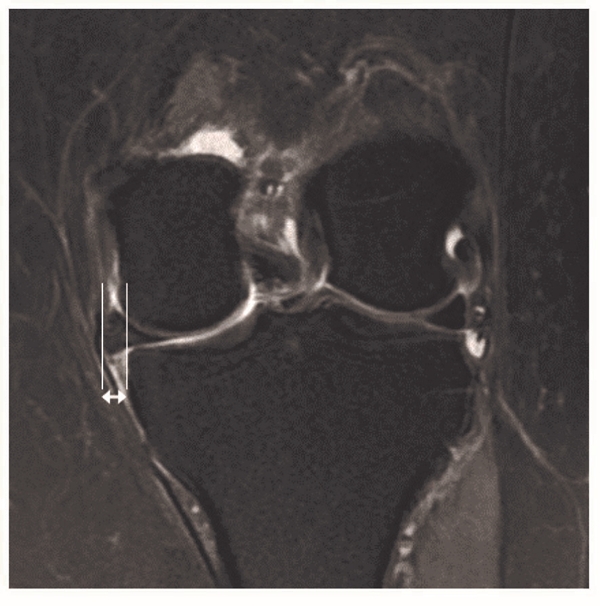

目前关于MMPRTs手术疗效评估指标主要包括了临床评估和影像学评估两方面。临床评估一般采用Lysholm评分量表、IKDC(International Knee Documentation Committee)评分量表,HHS(Hospital for Special Surgery score)评分量表以及Tegner activity score评分量表等对膝关节功能进行主观的评估,其中最常见的为Lysholm评分量表,其次为IKDC评分量表。影像学评估内容包括了MRI评估和X线评估。一般采取常规序列的MRI检查来评估半月板的愈合情况、半月板外突的情况以及软骨损伤情况。其中半月板愈合分为完全愈合(MRI三个平面上均无半月板断裂信号)、部分愈合(MRI三个平面中1个或2个平面出现半月板断裂信号)和不愈合(MRI三个平面上均出现半月板断裂信号)。内侧半月板外突是通过内侧胫骨边缘的正切垂线和内侧半月板外侧缘正切垂线之间距离进行评估(图4)。X线评估一般通过站立位正侧位或者膝关节屈曲45°位的X线片来评估患者关节间隙的狭窄情况,并进行Kellgren-Lawrence(K-L)分级,进一步评估患者骨关节炎的进展情况。

图4 MRI冠状位显示内侧半月板外突 箭头所示为半月板外突的距离